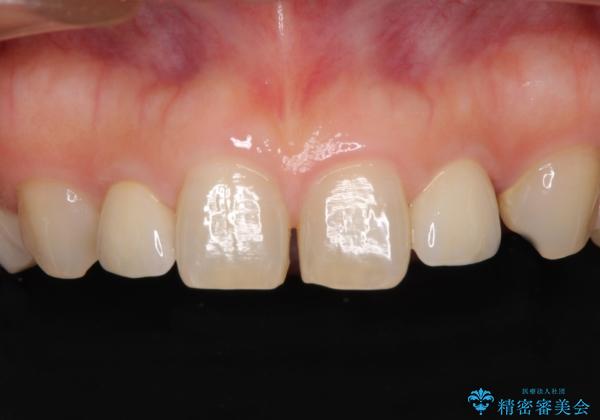

前歯の隙間や、周りの歯と色合いの違いなどはあまり気にしていらっしゃらなかったため、矮小歯の2歯を自然な大きさに仕上げました。

とても自然な歯が装着されたとのことで、患者様には大変満足していただきました。